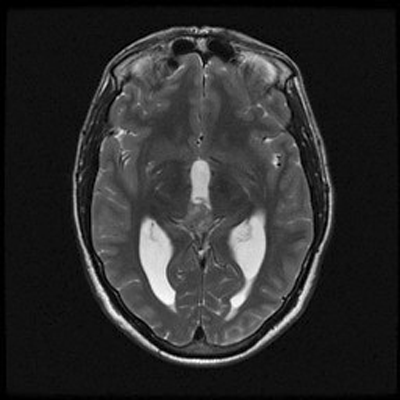

An MRI of the brain with and without contrast revealed a 2.6 x 1.3 x 1.6 cm  (AP x CC X W) heterogenous lesion within the region of the pineal gland and projecting into the third ventricle. The lesion had both solid and cystic components and demonstrated heterogenous enhancement on T1-weighed images. The enhancement is located medial to the veins of Rosenthal, inferior to the cerebral veins, and posterior to the vein of Galen. The mass is isointense to the cortex on T2-weighed images. No significant midline shift or significant edema was observed. The ventricular system was prominent in size, consistent with mild hydrocephalus. Basilar cisterns were preserved and normal cerebrovascular flow-voids were seen.  No abnormalities of the cerebellar or cerebral parenchyma, the brainstem or the cervical spinal cord were observed. Dural venous sinuses and meninges were unremarkable. Regions of the orbit and sella were unremarkable. Paranasal sinuses demonstrated paranasal sinus disease of the bilateral maxillary and left ethmoidal sinuses.

The patient was placed on dexamethasone and a third ventriculostomy with endoscopic biopsy of the pineal mass was performed. As per the neurosurgeon, the tumor appeared pedunculated. The following are representative images.

B.

T2